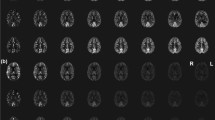

The multiband technique allows the acquisition of more slices within a given volume coverage at higher SMS factors, enabling each slice to be thinner than the slices acquired using the SB technique. This feature was utilized to increase the number of slices per volume when increasing the acceleration factor and reducing the slice thicknesses (4-6 mm) and partial volume in the slice direction. A prototype 2D EPI sequence was used with SMS factors of 1, 3, 4 and 6, leading to the optimized number of slices and hence the achievable slice thickness and brain coverage, as shown in Fig. 1. Detailed MRI parameters are listed in Table 1.

Summary of study design illustrating brain coverage and acquisition strategies using optimized protocols exploiting different simultaneous-multi slice acceleration factors (SMS). Number of colors in brain coverage indicates the SMS acceleration factor used and lines represents total number of slices acquired in each case: for every excitation one slice in each color group is acquired simultaneously in an ascending order

Using SMS acceleration, the image acquisition window was reduced from 1131 ms for 2D P1S1 to 386 ms for 2D P1S3 and 2D P1S4 and 288 ms for 2D P1S6. Representative control images for each protocol variant and the corresponding absolute CBF color maps from one subject are shown in Fig. 1.